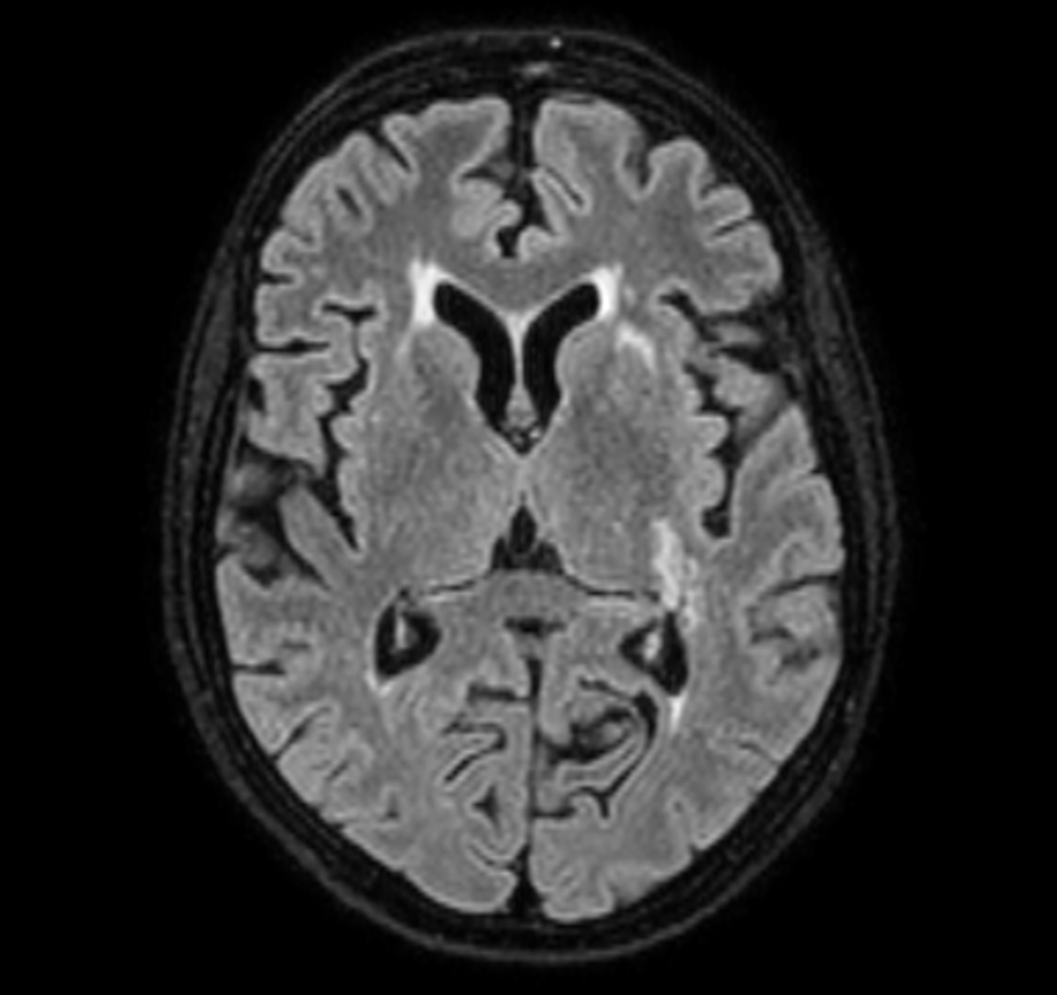

3D VIEW - T2w FLAIR (axial reformat)

-